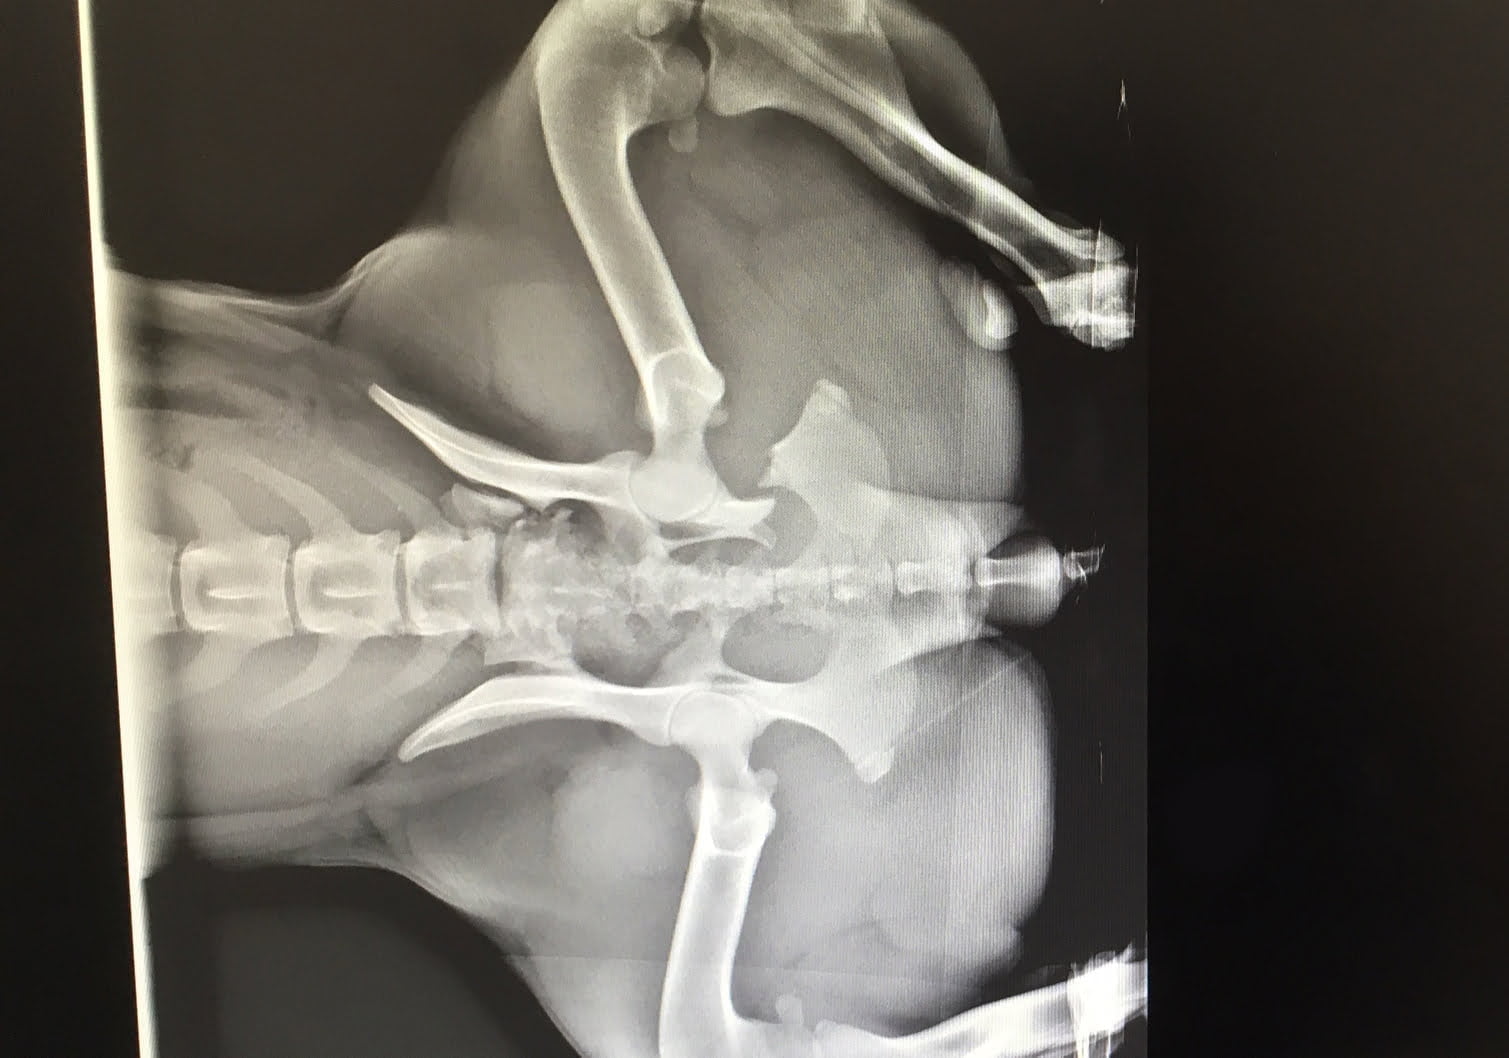

After being hit by a car, Mia, a 3-year-old dog, was brought to the Montreal SPCA by a good Samaritan who found her in an injured state. Upon her arrival, she was in obvious pain and was struggling to walk. Our veterinary team was immediately able to assess the severity of her injuries using our new X-ray machine.

Mia’s X-rays quickly revealed multiple pelvic fractures. Fortunately, considering her clinical symptoms, surgery was not necessary and Mia’s prognosis was good. She needed to be given painkillers and had to remain immobile for a period of eight weeks to allow her fractured bones to heal. During her recovery, a few follow-up X-rays were taken to ensure that her injury was healing properly.